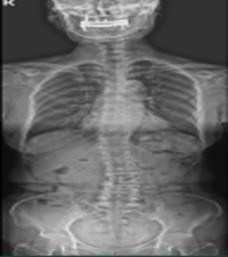

그림9.jpg 촬영 일시: 2025.05.30

<Fig 1. 척추 X-Ray 영상>

저는 즉시 정밀 검사를 제안했습니다.

당일 MRI와 근육 검사까지 진행한 결과?

정말 놀라운 사실들이 드러났습니다.

1️⃣ 요추 퇴행성 디스크

2️⃣ 요추 4-5번 전방전위증

3️⃣ 경추 6-7번 디스크 탈출증

4️⃣ 척추 측만증

5️⃣ 근감소증

6️⃣ 자율신경 기능 장애에 의한 늑간신경통